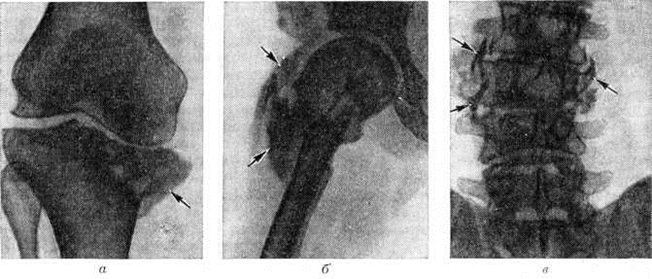

Рис. 1.

Микропрепараты поперечных срезов спинного мозга в грудном (а) и крестцовом (б) отделах при спинной сухотке: область дегенерации задних канатиков указана стрелками; окраска по Вейгерту; ×7.